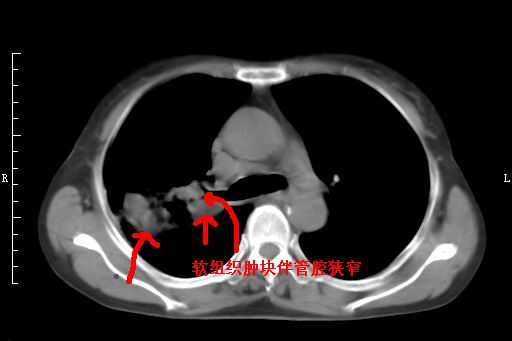

标题: CT27173:右上叶后段肺癌 [打印本页]

标题: CT27173:右上叶后段肺癌

右上叶后段肺癌伴阻塞性炎症(肺脓肿形成)

支持楼主【气管腔狭窄定性癌肿意义大】